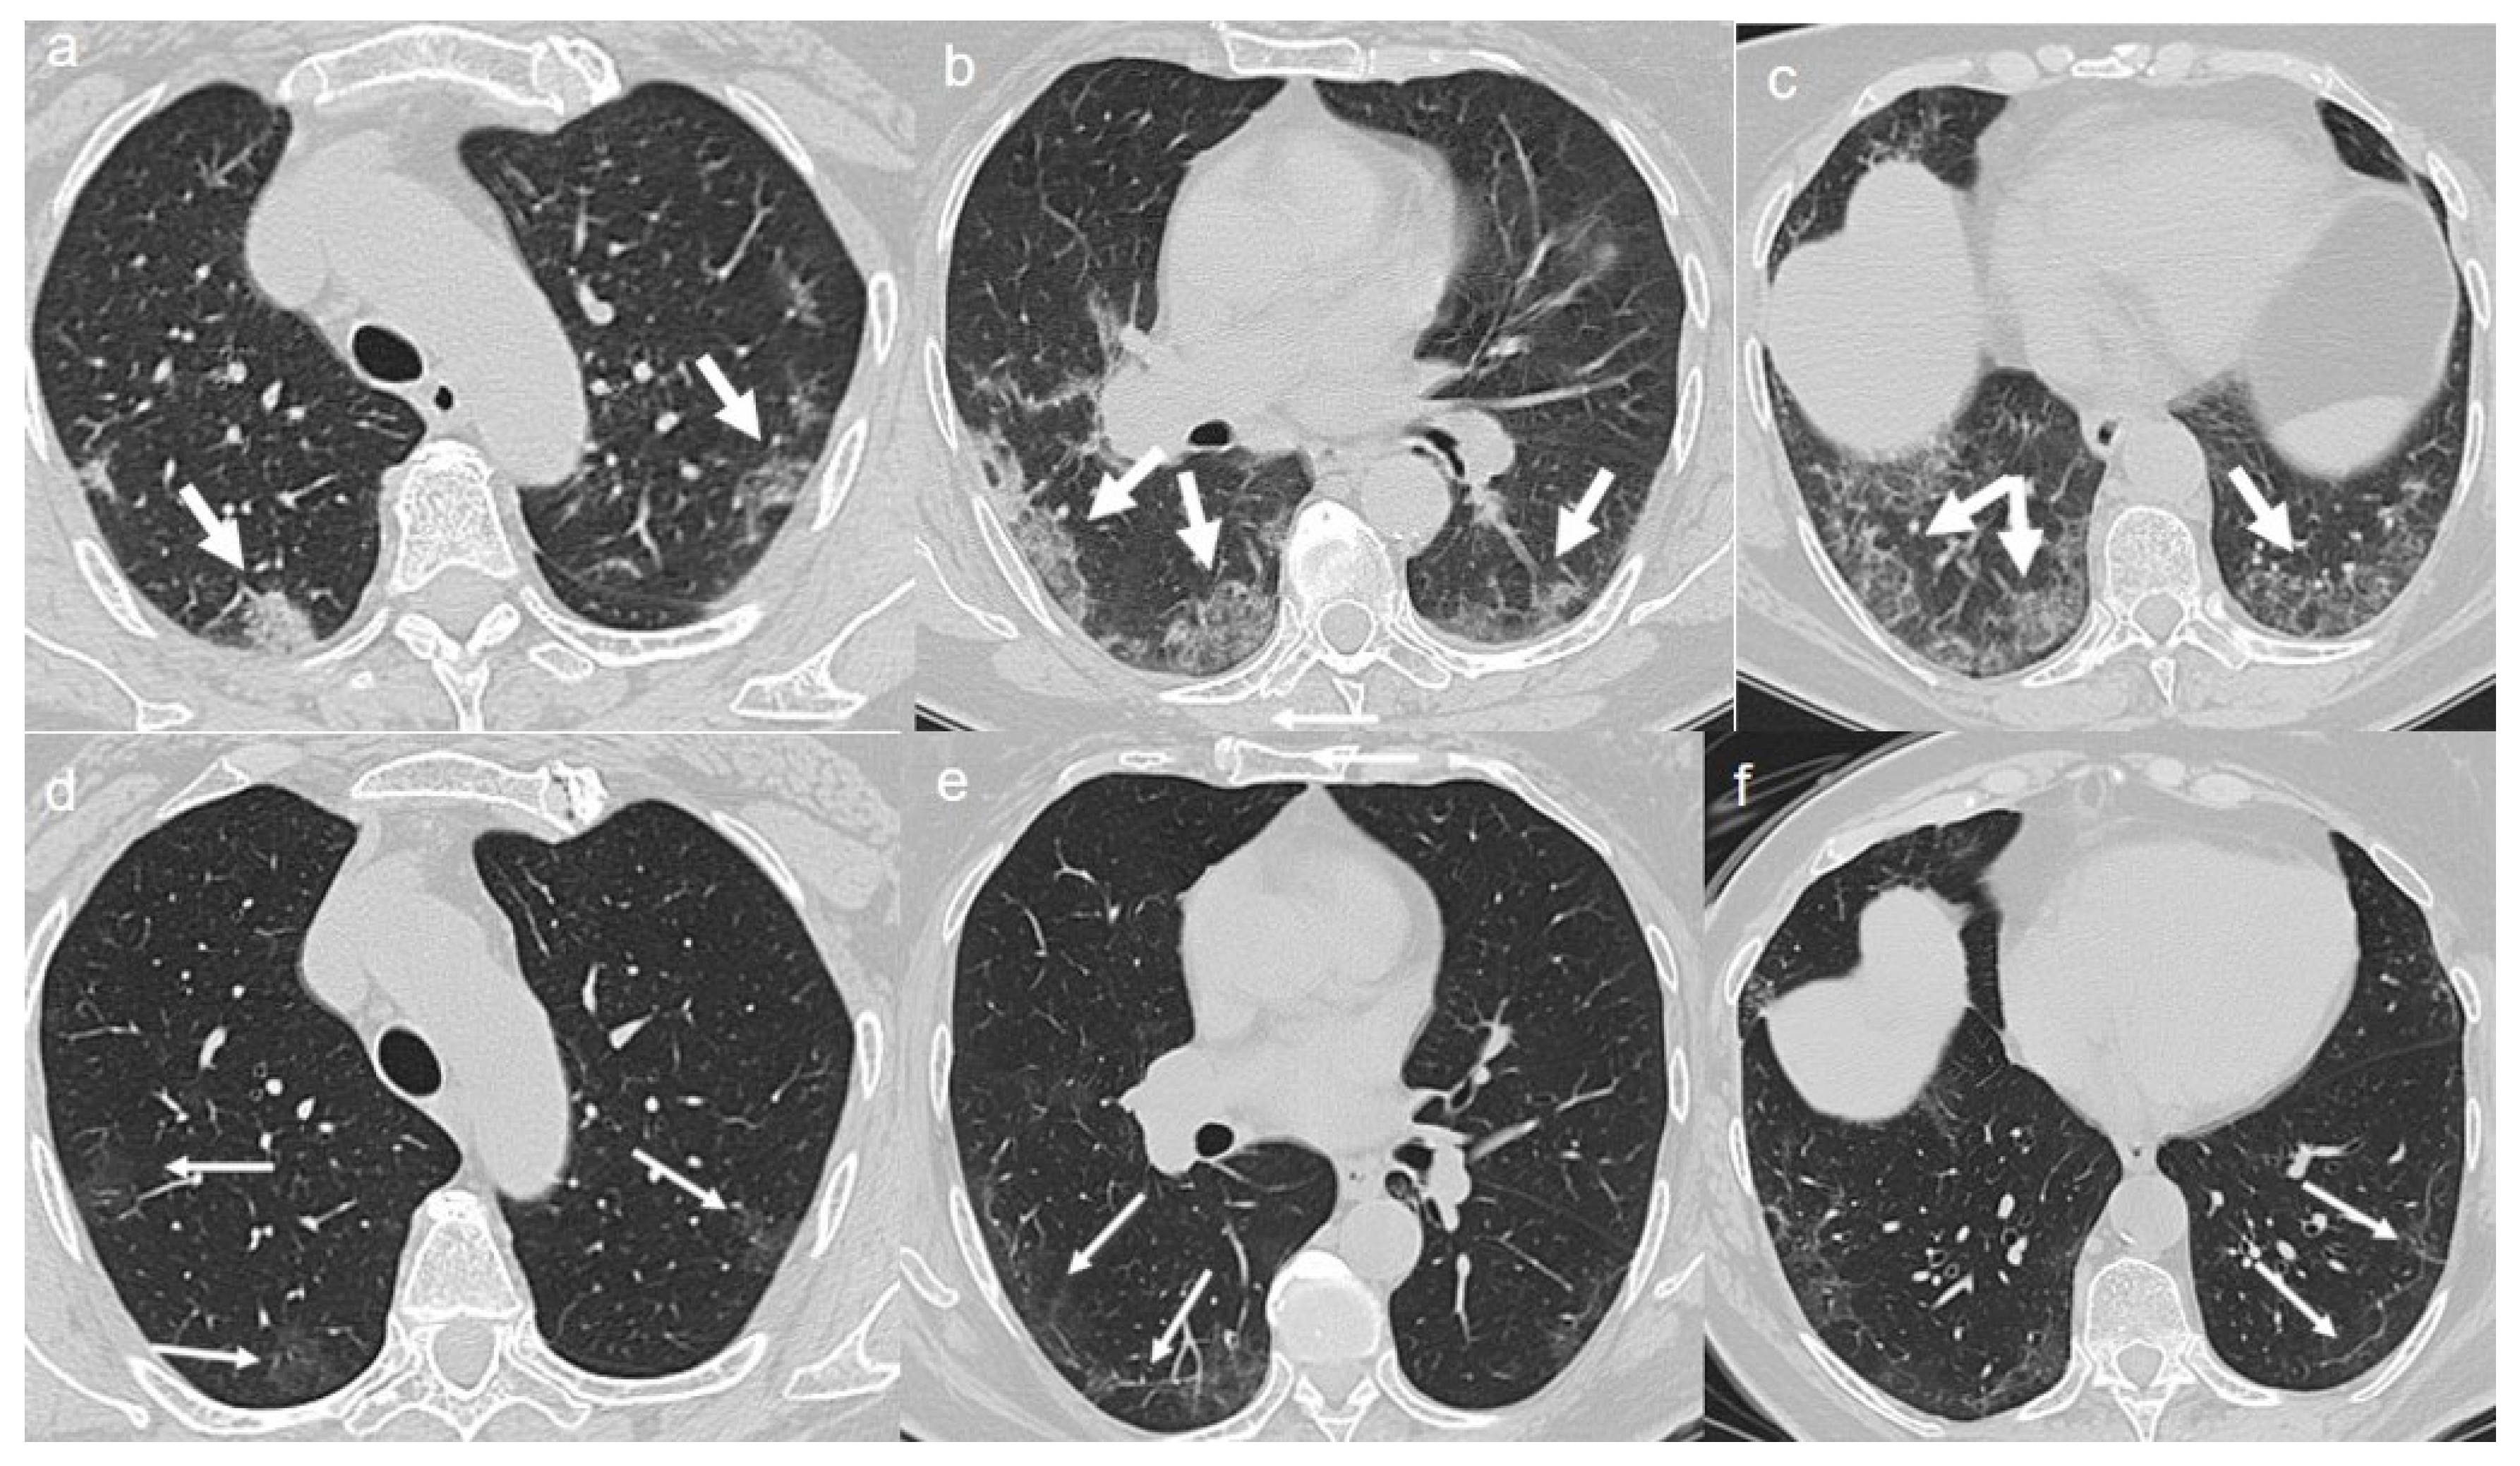

2.6. Case 6

On admission, chest CT showed bilateral extensive areas of GGO and consolidations, with prevalent peripheral distribution in the upper and lower lobes (Figure 7a–c).

A CT at 4 months from the onset of symptoms showed the persistence of diffuse thickening of the interlobular septa, with fibrotic appearance (Figure 7d,e); air bubble sign with bronchiectasis (Figure 7f) was also recognizable. An air bubble sign consists of a small air-containing space that can result from a dilatation of a physiological space or from lung cystic changes or can be related to consolidation resorption.

Figure 7. (ac) CT shows bilateral extensive areas of GGO and consolidations, with prevalent peripheral distribution, in upper and lower lobes (arrows). (df) Follow up CT 4 months after admission shows persistence of diffuse thickening of the interlobular septa, with fibrotic appearance (thin arrows in d,e); air bubble sign with bronchiectasis (thin arrows in f) is recognizable.